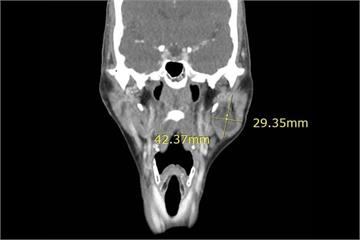

{PLAYICON}婦人左臉突然「凸」一塊! 4公分腫塊竟是少見腺細胞癌